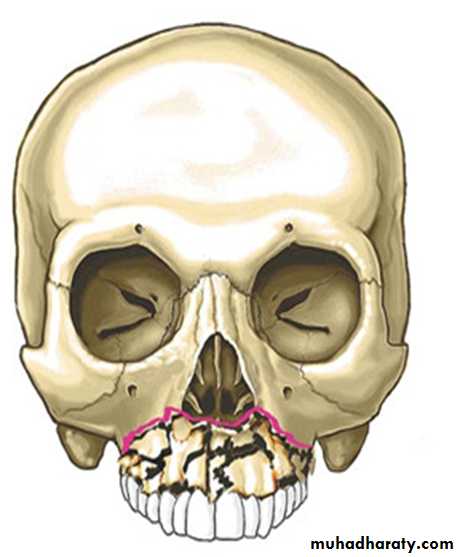

• 1-Maxillary Fractures:

• First described by an anatomist René Le Fort in 1901.

• Le Fort I — A transverse fracture resulting in a floating palate.

• Le Fort II — A pyramidal fracture that traverses the infraorbital rims and nasoethmoid region producing midface mobility.

• Le Fort III — A fracture through the zygoma,orbital floor and nasal bridge that results in craniofacial dysjunction.

Le Fort classification of maxillary fractures

• The Le Fort II fracture is the most common, followed by Le Fort I and III patterns.